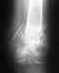

Каждый раз диагноз писали Травматический вывих плеча. Плечо действительно не выпадает при простых движениях. 2 раза причина - падение, 1 раз - очень резкое движение в бассейне. Снимки есть со 2го вывиха, и надеюсь получить с последнего. Насколько помню, каждый раз кость уходила вниз и внутрь.Еще у меня есть диагноз Дисплазия соединительных тканей.Мне 29 лет. Хотелось бы в дальнейшем вести активный образ жизни, заниматься любительским спортом.